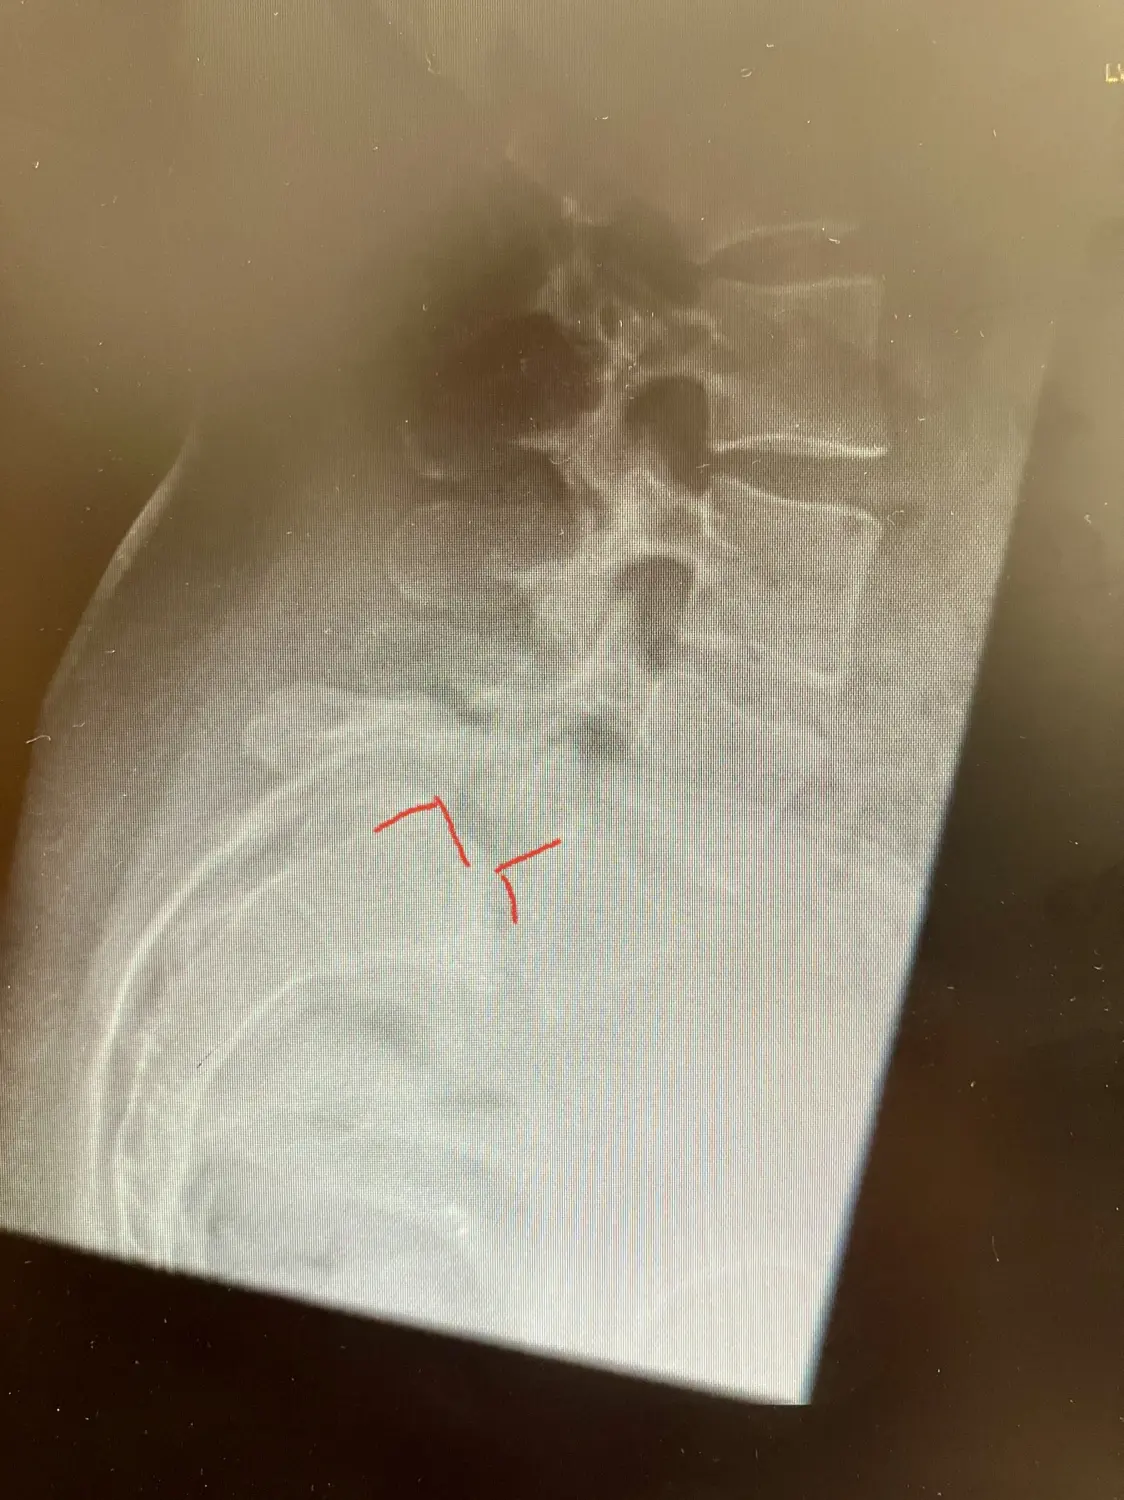

Als Spondylolisthese bezeichnet man das Abgleiten eines Wirbelkörpers im Verhältnis zum darunterliegenden Wirbelkörper. Das Abgleiten führt zu einer Instabilität der Wirbelsäule, die zu Schmerzen, eingeschränkter Beweglichkeit und auch Kompression der Nervenwurzeln führen kann. Am häufigsten sind die Bewegungssegmente der unteren Lendenwirbelsäule (L5/S1 oder L4/5) betroffen. Die Ursache für ein Wirbelgleiten kann angeboren sein oder durch Faktoren wie Verletzungen, Degeneration der Bandscheiben oder Überlastung der Wirbelsäule verursacht werden. Als Spondylodese wird die operative Stabilisierung des Gleitwirbels bezeichnet.